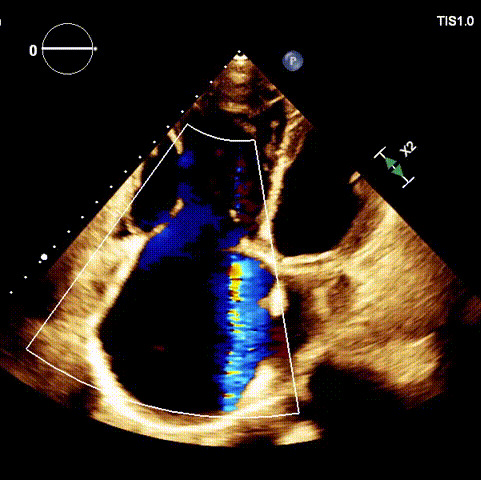

1.二尖瓣位機械瓣位置及功能未見異常;2.雙房及右室明顯擴大(左房收縮容積115ml,右房收縮容積370ml,右室中段左右徑65mm,右室FAC37%),下腔靜脈及冠狀靜脈竇擴張(下腔靜脈直徑44mm,冠狀靜脈竇直徑22mm);3.極重度三尖瓣反流(FTR 6+)。

術前超聲